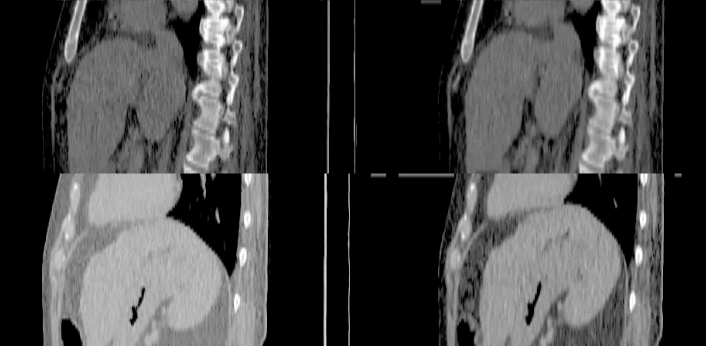

UBC PhD project (2019-2023): saliva retention and recovery after radiotherapy focusing on use of novel quantitative CT, MR, and PET imaging techniques to personalize treatment. (Caleb Sample.)

UBC Engineering Physics Capstone project (2020/2021 academic year): implementation of a pharmacokinetic tracer model for quantifying liver blood perfusion. (Jackson Gayda, Krysten Zissos, Mojan Jamalzadeh, and Tianna Hudak.)